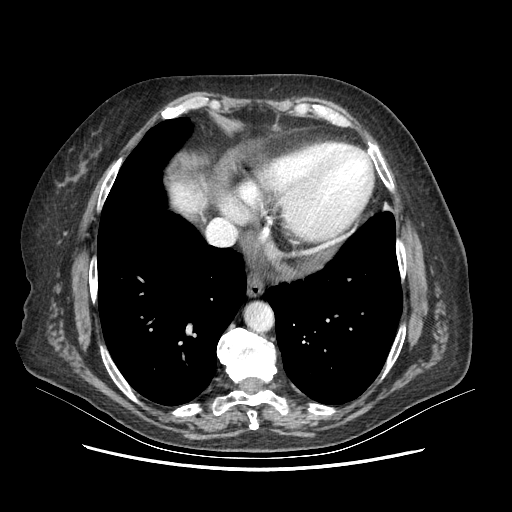

Generated VENOUS CT scan (A→B translation)

Full window (WL 1023.5, WW 4095 β†’ Low βˆ’1024, High +3071)

Lung window (WL -600, WW 1500 β†’ Low βˆ’1350, High +150)

Mediastinum window (WL 40, WW 400 β†’ Low βˆ’160, High +240)